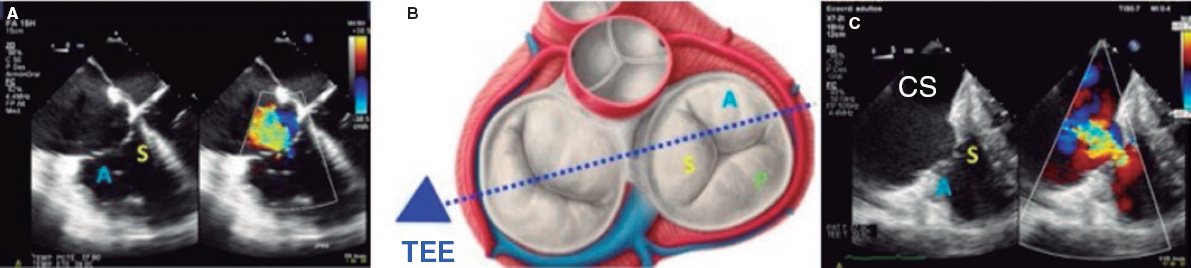

1. Mid-esophageal 4-chamber view at 0º. The septal leaflet (adjacent to the aorta) and the anterior leaflet (adjacent to the RV free wall) can be seen when the transducer is in anteflexion position (figure 1). The posterior leaflet can be seen when it is in the retroflexion position.

Figure 1. A: mid-esophageal 4-chamber view showing the septal leaflet and the anterior leaflet. B: imaginary view in the 4-chamber view. C: deep transesophageal view. A, anterior; TEE, transesophageal echocardiogram; S, septal; CS, coronary sinus.

To optimize the images of the right heart structures, the transducer should be turned clockwise. The artifacts of the septum and aortic or mitral valves can block the view of the septal leaflet. Tricuspid annulus is measured in this view with open flap-like cusps at the end of the diastole.

3. Deep esophageal 4-chamber view at 0°. Since the right inferior border of the heart is close to the diaphragm, the deepest insertion of the TEE transducer reaches the distal esophagus, close to the gastroesophageal junction; it may be that this view will only show the right atrium and coronary sinus and no images of the left atrium (figure 1). This prevents left heart structure-related artifacts from happening like the acoustic shadowing that the mitral prosthetic material can cause on the septal leaflet. This is the optimal view to acquire 3D volumes.